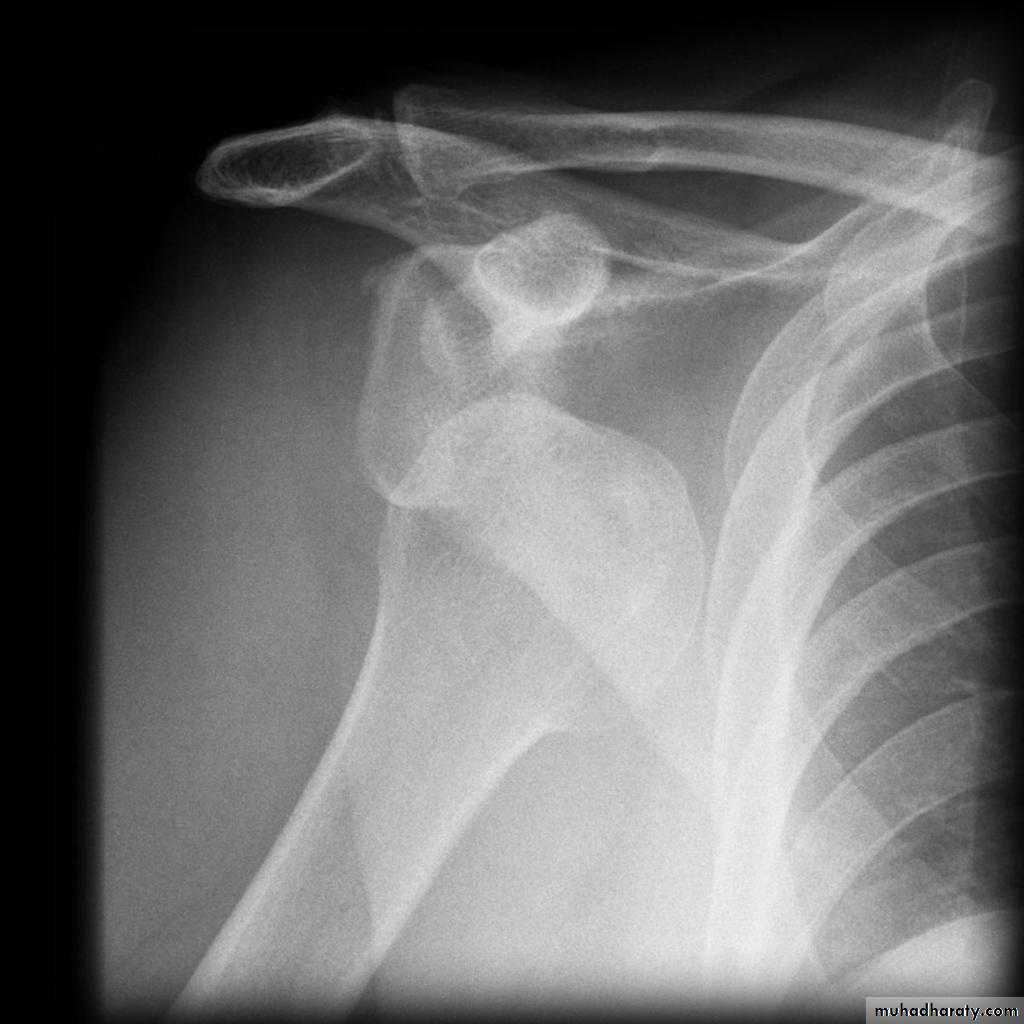

Fall on out stretched hand

40 years male fall on out streched hand